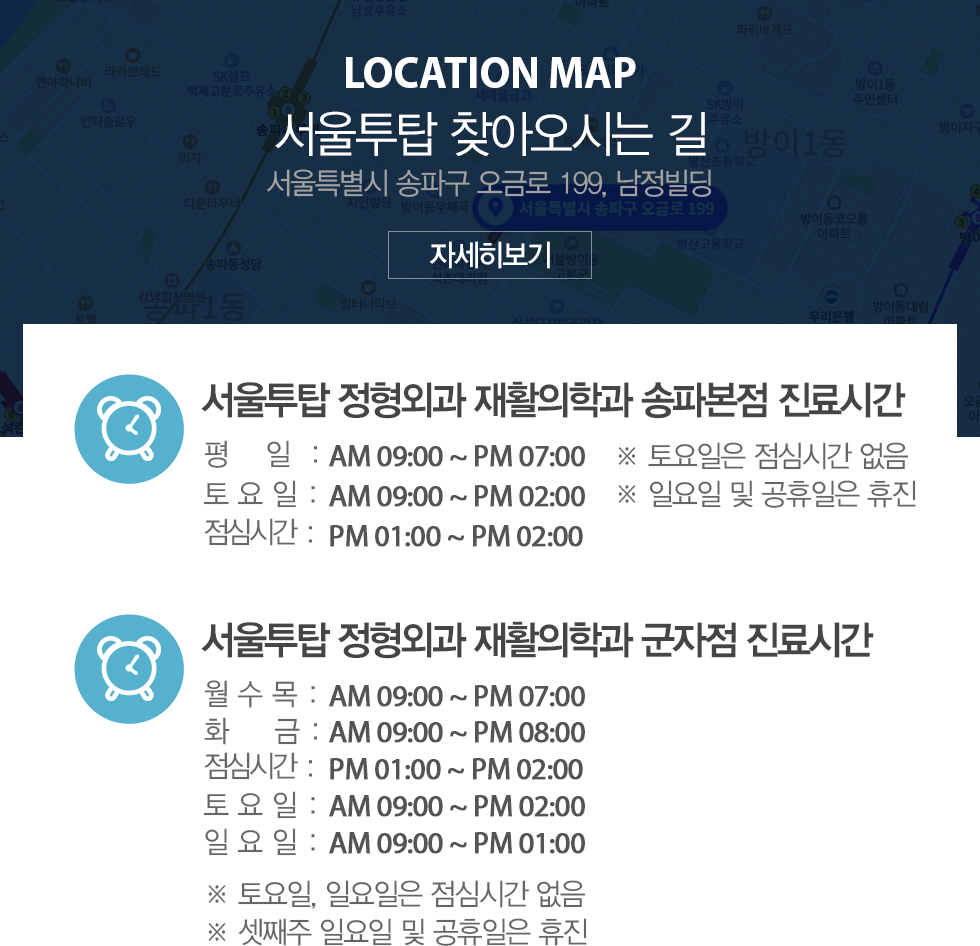

3. Ею, ПЗБИИЎ

ДСАё ПАСТ Йз АёР§, ДСАЃНХАцПА, ДСАЃБй ЦФП, ЦМПЁУїСѕШФБК, T4СѕШФБК, ЙйНКЦЎЗьКД

3. Ею, ПЗБИИЎ

ДСАё ПАСТ Йз АёР§, ДСАЃНХАцПА, ДСАЃБй ЦФП, ЦМПЁУїСѕШФБК, T4СѕШФБК, ЙйНКЦЎЗьКД

3. Ею, ПЗБИИЎ

ДСАё ПАСТ Йз АёР§, ДСАЃНХАцПА, ДСАЃБй ЦФП, ЦМПЁУїСѕШФБК, T4СѕШФБК, ЙйНКЦЎЗьКД

3. Ею, ПЗБИИЎ

ДСАё ПАСТ Йз АёР§, ДСАЃНХАцПА, ДСАЃБй ЦФП, ЦМПЁУїСѕШФБК, T4СѕШФБК, ЙйНКЦЎЗьКД